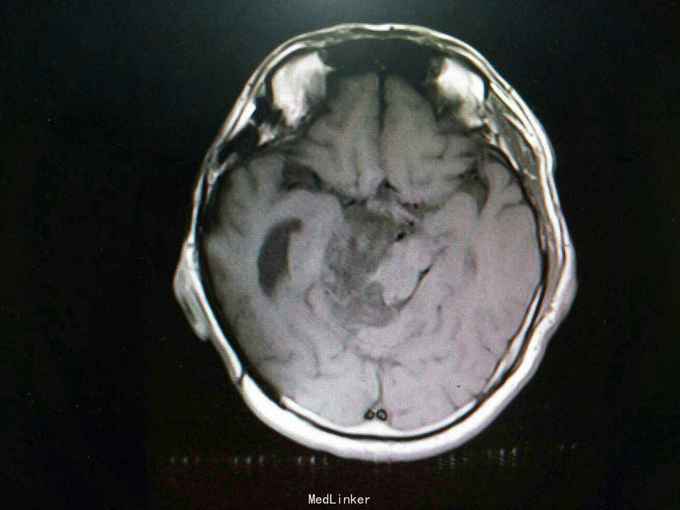

查体:生命体征平稳。神经系统检查:右侧眼睑下垂,左侧眼睑无下垂。肌力 右侧肢体肌力5-级,左侧肢体肌力正常。肌张力: 右上肢肌张力正常,右下肢肌张力正常;左上肢肌张力正常,左下肢肌张力正常。肌营养检查:四肢肌肉无萎缩。共济与平衡检查:正常。外院颅脑CT示右侧桥脑小脑角团片囊性低密度区,性质待定,蝶窦右后方局部骨质缺损代之稍低密度软组织肿块,考虑原肿瘤复发,颅骨呈术后改变,颅脑CT增强示颅内占位性病变(表皮样囊肿?)。入院后行颅脑MRI检查提示: 右侧颞骨岩尖-脚间池-右侧环池-右侧桥小脑角池见片状异常信号影,边界清,形态不规则,呈匍匐状分布,冠状位范围约47mm×29mm。相应右侧颞、脑干明显受压,脑干向左移位。第三脑室略向左移位。右侧额骨、颞骨骨皮质欠连续,呈术后改变。 考虑右侧颞骨岩尖-脚间池-右侧环池-右侧桥小脑角池表皮样囊肿。 右侧颅骨呈术后改变。